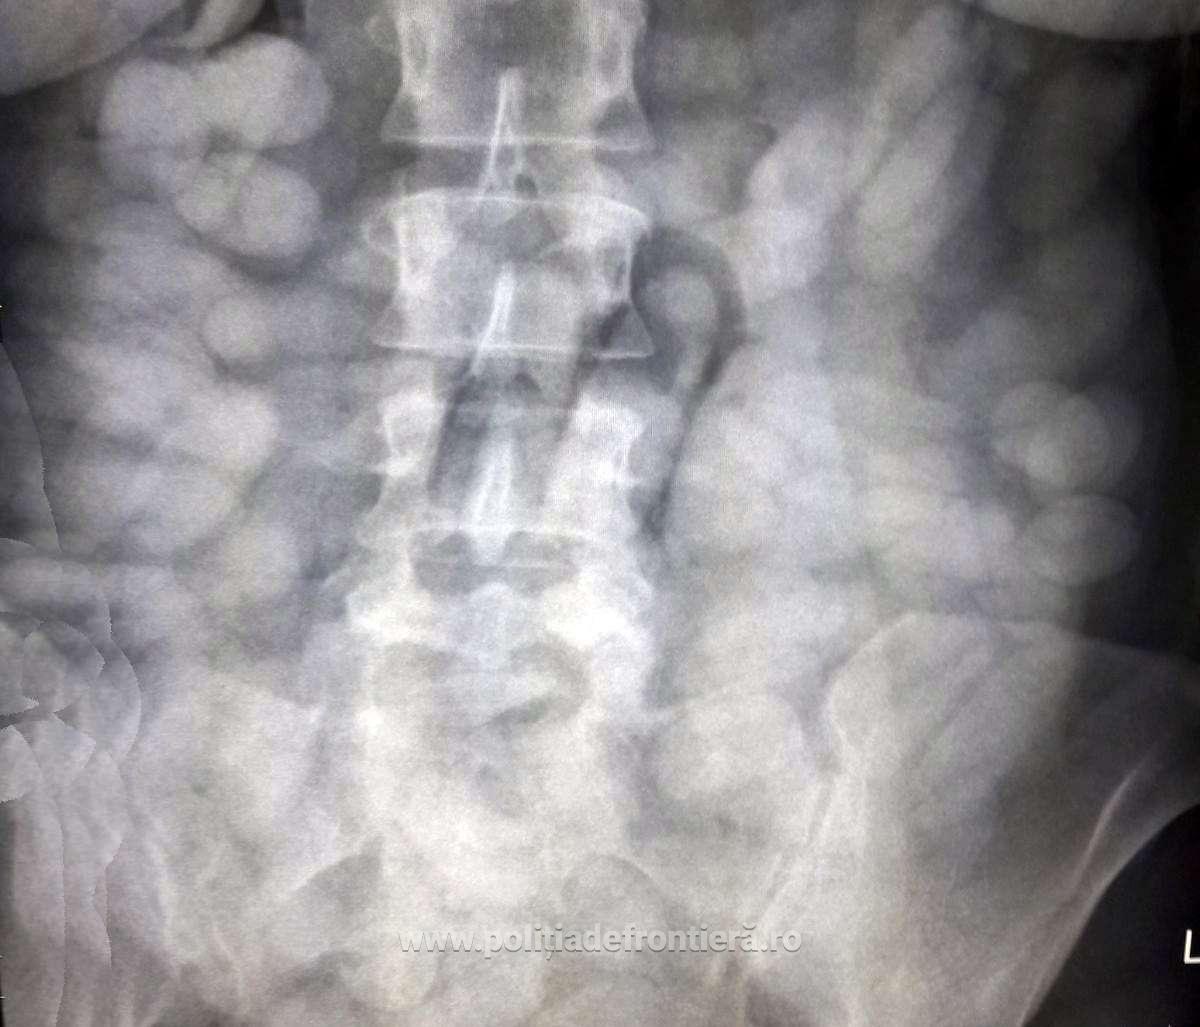

Existând suspiciuni că transportă substanţe interzise, persoanele în cauză au fost supuse unui control cu raze X, cu aparatul aflat în dotarea Poliţiei de Frontieră din cadrul Aeroportul Internaţional Henry Coandă.

Cu această ocazie s-a constatat că două dintre persoane, Verice R. şi Weslley L. aveau zeci de capsule ingerate în stomac.